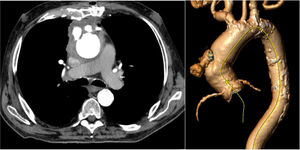

An 80-year-old man, with multiple comorbidities and history of aortic valve replacement and pericardial patch repair of the ascending aorta several years prior, presented to the emergency department with mild bleeding from a sternal wound and a pulsatile mass below the wound. Computed tomography showed sternal osteomyelitis, periaortic hematoma, and cutaneous fistulae (figure 1). Blood tests showed raised inflammatory markers and positron emission tomography was positive for infection in the ascending aorta.